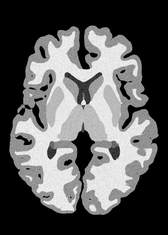

4.2 Registration to a 100 micron ex-vivo brain MRI volume

To showcase the efficacy of our method on real large scale images, we register a 250 in-vivo MRI image (Lüsebrink et al., 2017) to a 100 ex-vivo FLASH human brain volume (Edlow et al., 2019). This represents an inverse problem with more than 11.2B optimizable parameters (compared to 20M for clinical datasets), or 44.8GB of GPU memory. The entire problem does not fit on most GPUs, necessitating distributed multimodal registration. We optimize a composite transform - affine followed by a diffeomorphic mapping; details can be found in Section E.1. Multimodal deformable registration took 58 seconds on 8 NVIDIA A6000 GPUs, which is unprecedented at this resolution. Fig. 6 shows qualitative results, highlighting the ability to register highly detailed structures such as cerebellar white matter; these structures are not visible at macroscopic scales. The resultant advantages of performing registration at this scale can allow researchers to characterize the neuroanatomy at microscopic resolutions and allow morphometric analysis of cortical layers and subcortical nuclei among other structures.